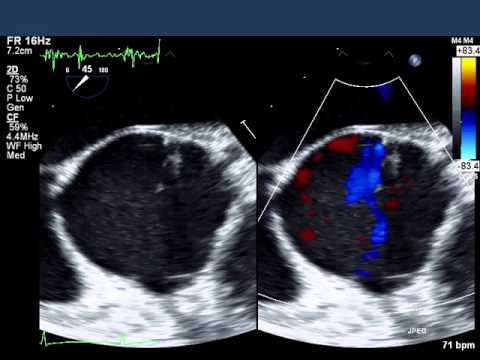

本誌図2

A:経胸壁心エコー図、B:経食道心エコー図

A上段:経胸壁心エコー図長軸像で拡大したvalsalvaが洋ナシのような形態をしている。

A下段:経胸壁心エコー図心尖部3腔像。大動脈逆流を認める。

B上段:経食道心エコー図長軸像で拡大したvalsalvaを認める。大動脈弁逆流は中央から認められ、弁接合の中心の接合が不良である。

B下段:経食道心エコー短軸像。弁は三尖だがバランスが不良で中央に小さな隙間があるのがわかる。ここから大動脈弁逆流ジェットが認められる。

LA:左房、LV:左室、Ao:大動脈、NCC;大動脈弁無冠尖、LCC;大動脈弁無冠尖、RCC;大動脈右冠尖

LA:左房、LV:左室、Ao:大動脈